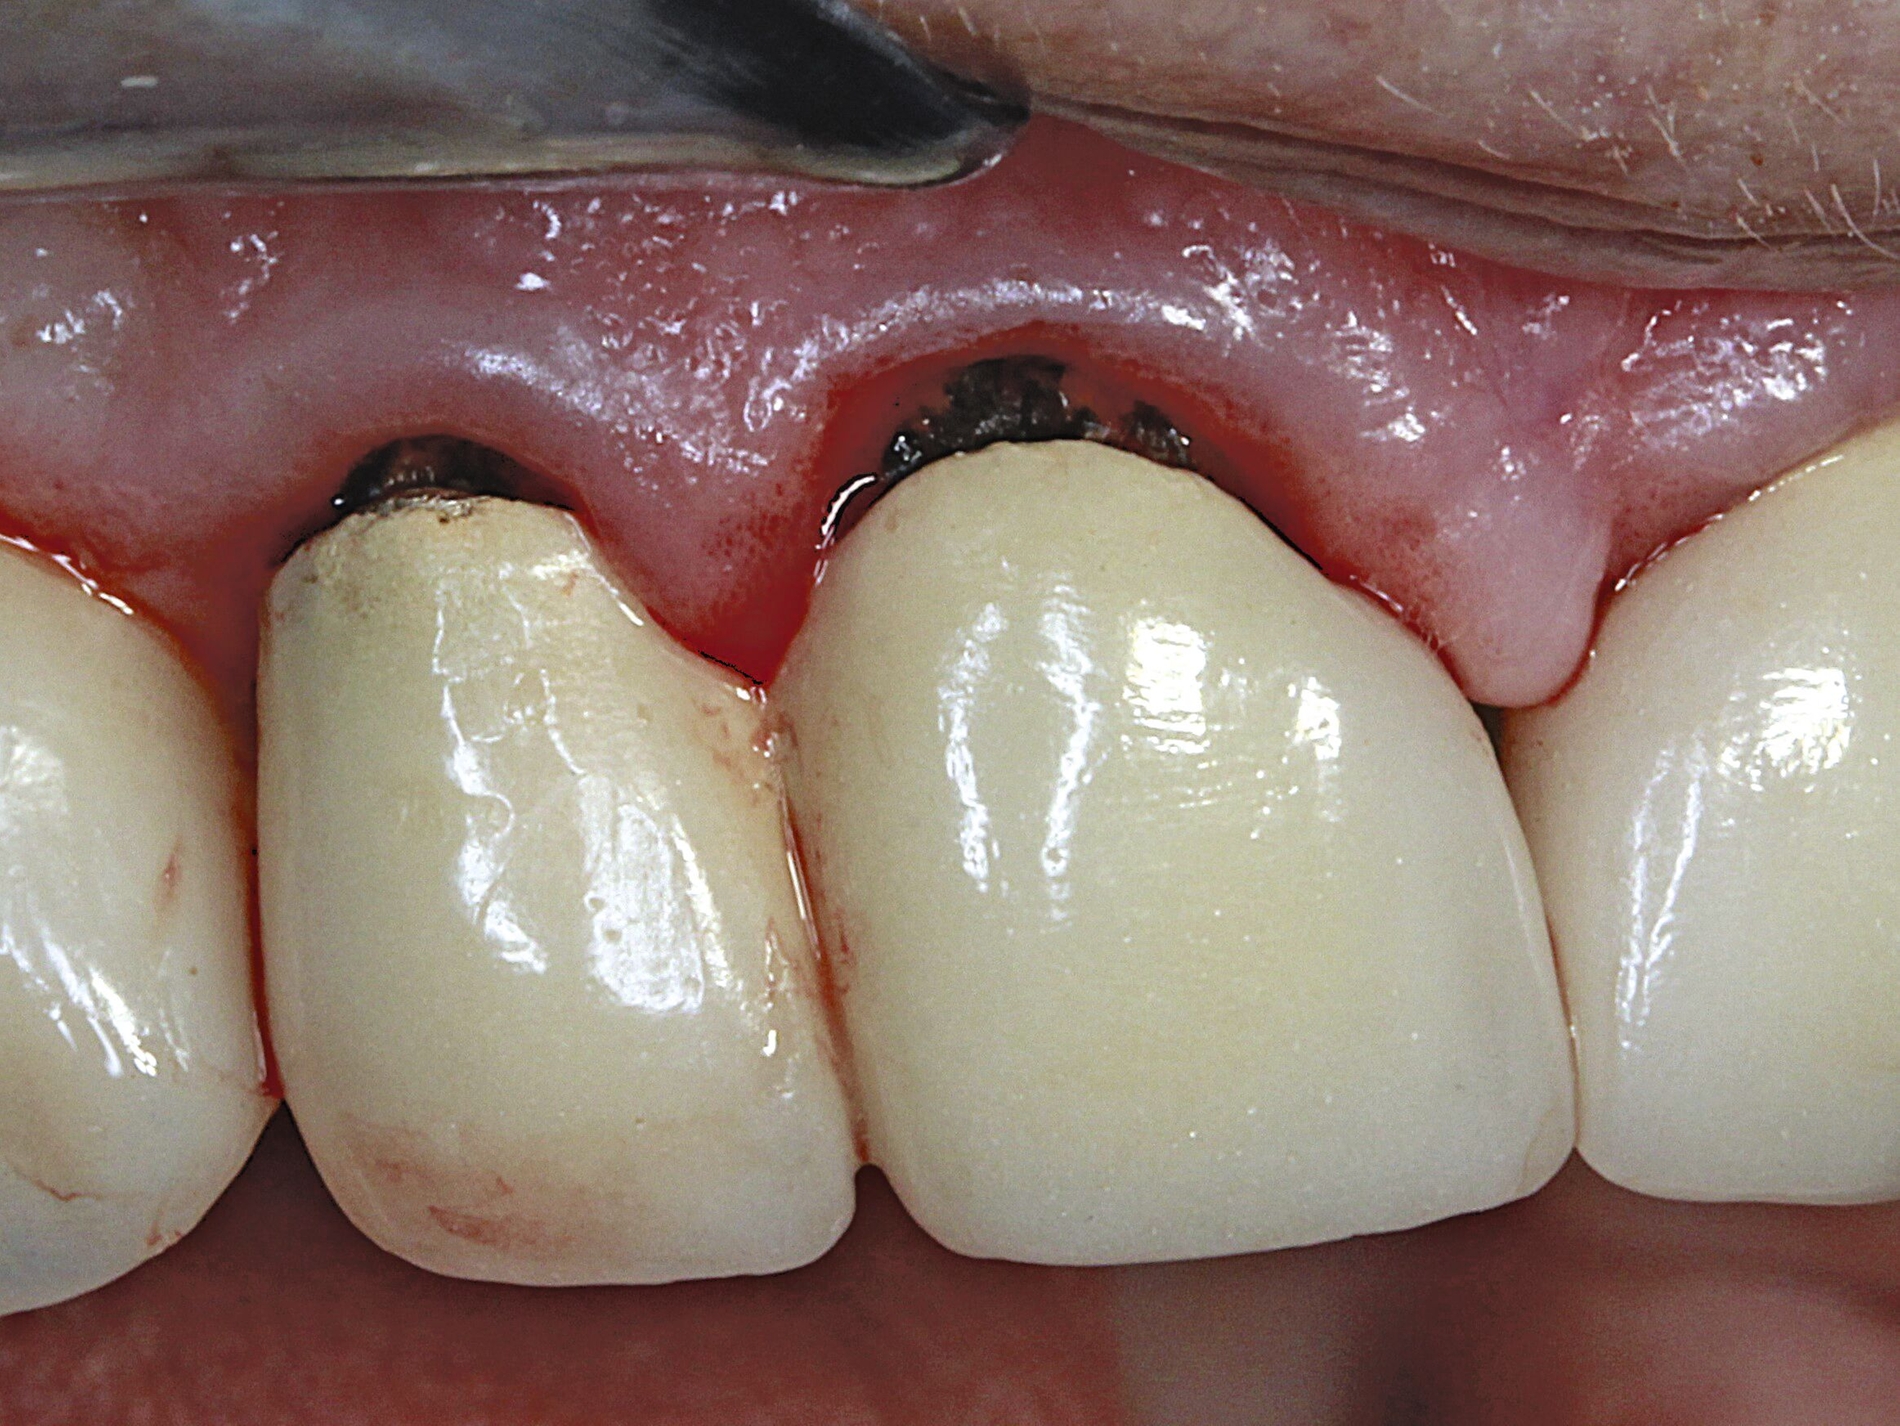

Silberdiamminfluorid ist eine wasserlösliche Verbindung, die aus Silberionen (Ag+), Ammoniak (NH₃) und Fluoridionen (F-) besteht. Ammoniak dient in dieser Verbindung als Stabilisator, indem es die Lösung alkalisch hält. Bei einer Konzentration von 38 Prozent entspricht das einer Konzentration von 44.800 ppm Fluorid und 255.000 ppm Silberionen. In seiner physikalischen Erscheinung ist SDF eine klare bis leicht gelbliche Flüssigkeit mit einem charakteristischen metallischen und leicht ammoniakartigen Geruch. Aufgrund der hohen Alkalität kann es bei Schleimhautkontakt zu leichten Reizungen kommen (Abbildung 2).

Eine bekannte Nebenwirkung bei Anwendung auf kariösen Läsionen ist die Schwarzfärbung des behandelten Bereichs (Abbildungen 3, 4). Verfärbungen können aber auch bei Applikation auf kariesfreien Wurzeloberflächen entstehen, diese sind jedoch mit einer professionellen Zahnreinigung gut zu entfernen (Abbildung 2).

Der Wirkungsmechanismus ist bislang nicht aufgeklärt. Die wesentlichen Verbindungen in SDF-behandelten Läsionen sind Silberphosphat, Silberoxid und Silbersulfid. Silberphosphat ist ein guter Photokatalysator [Yi et al., 2010], der spezifische chemische Reaktionen mit oder zwischen den verschiedenen beteiligten Verbindungen und Zahnstrukturen induzieren oder aber die auch ohne Licht eintretenden Reaktionen einfach beschleunigen könnte. Es wird vermutet, dass beispielsweise metallische Silbernanopartikel entstehen könnten [Li et al., 2019]. Abbildung 3 zeigt bräunliche Verfärbungen der Schleimhaut nach Lichteinwirkung.